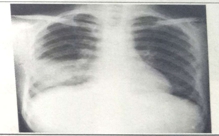

临床执业医师实践技能考试模拟题——影像学(6分)